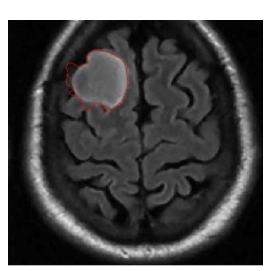

5.4 Results on brain MRI images

To achieve accurate segmentation of medical images, we have carefully tuned the parameters α, λ, and μ, which play a critical role in the performance of the DRLSE algorithm. These parameters control key aspects of the level set evolution, such as the smoothness of the contour (α), the fitting to the object boundaries (λ), and the regularization of the level set function (μ).

Using an empirical approach, we iteratively adjusted these values to obtain the best segmentation results for the images shown in Figure 10. Specifically, for brain MRIs, we found that setting α=0.5, λ=6, and μ=0.02 provided optimal segmentation results. These values effectively balance the trade-off between contour smoothness and accuracy in detecting object boundaries.

The segmentation process required several iterations to refine these parameters, highlighting the importance of adapting them to the specific characteristics of the images being analyzed. The results confirm the robustness of the DRLSE algorithm in delimiting structures in medical images.

Figure 10. Segmentation result. with the DRLSE algorithm